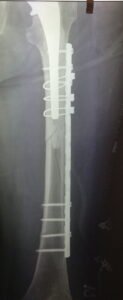

- Περιπροθετικό κάταγμα. Κάταγμα του οστού σε γειτνίαση με ορθοπεδικό εμφύτευμα. Διακρίνεται το κάταγμα κάτωθεν του εμφυτεύματος.

- Περιπροθετικό κάταγμα ανάμεσα σε δύο εμφυτεύματα με αστοχία της πλάκας οστεοσύνθεσης.